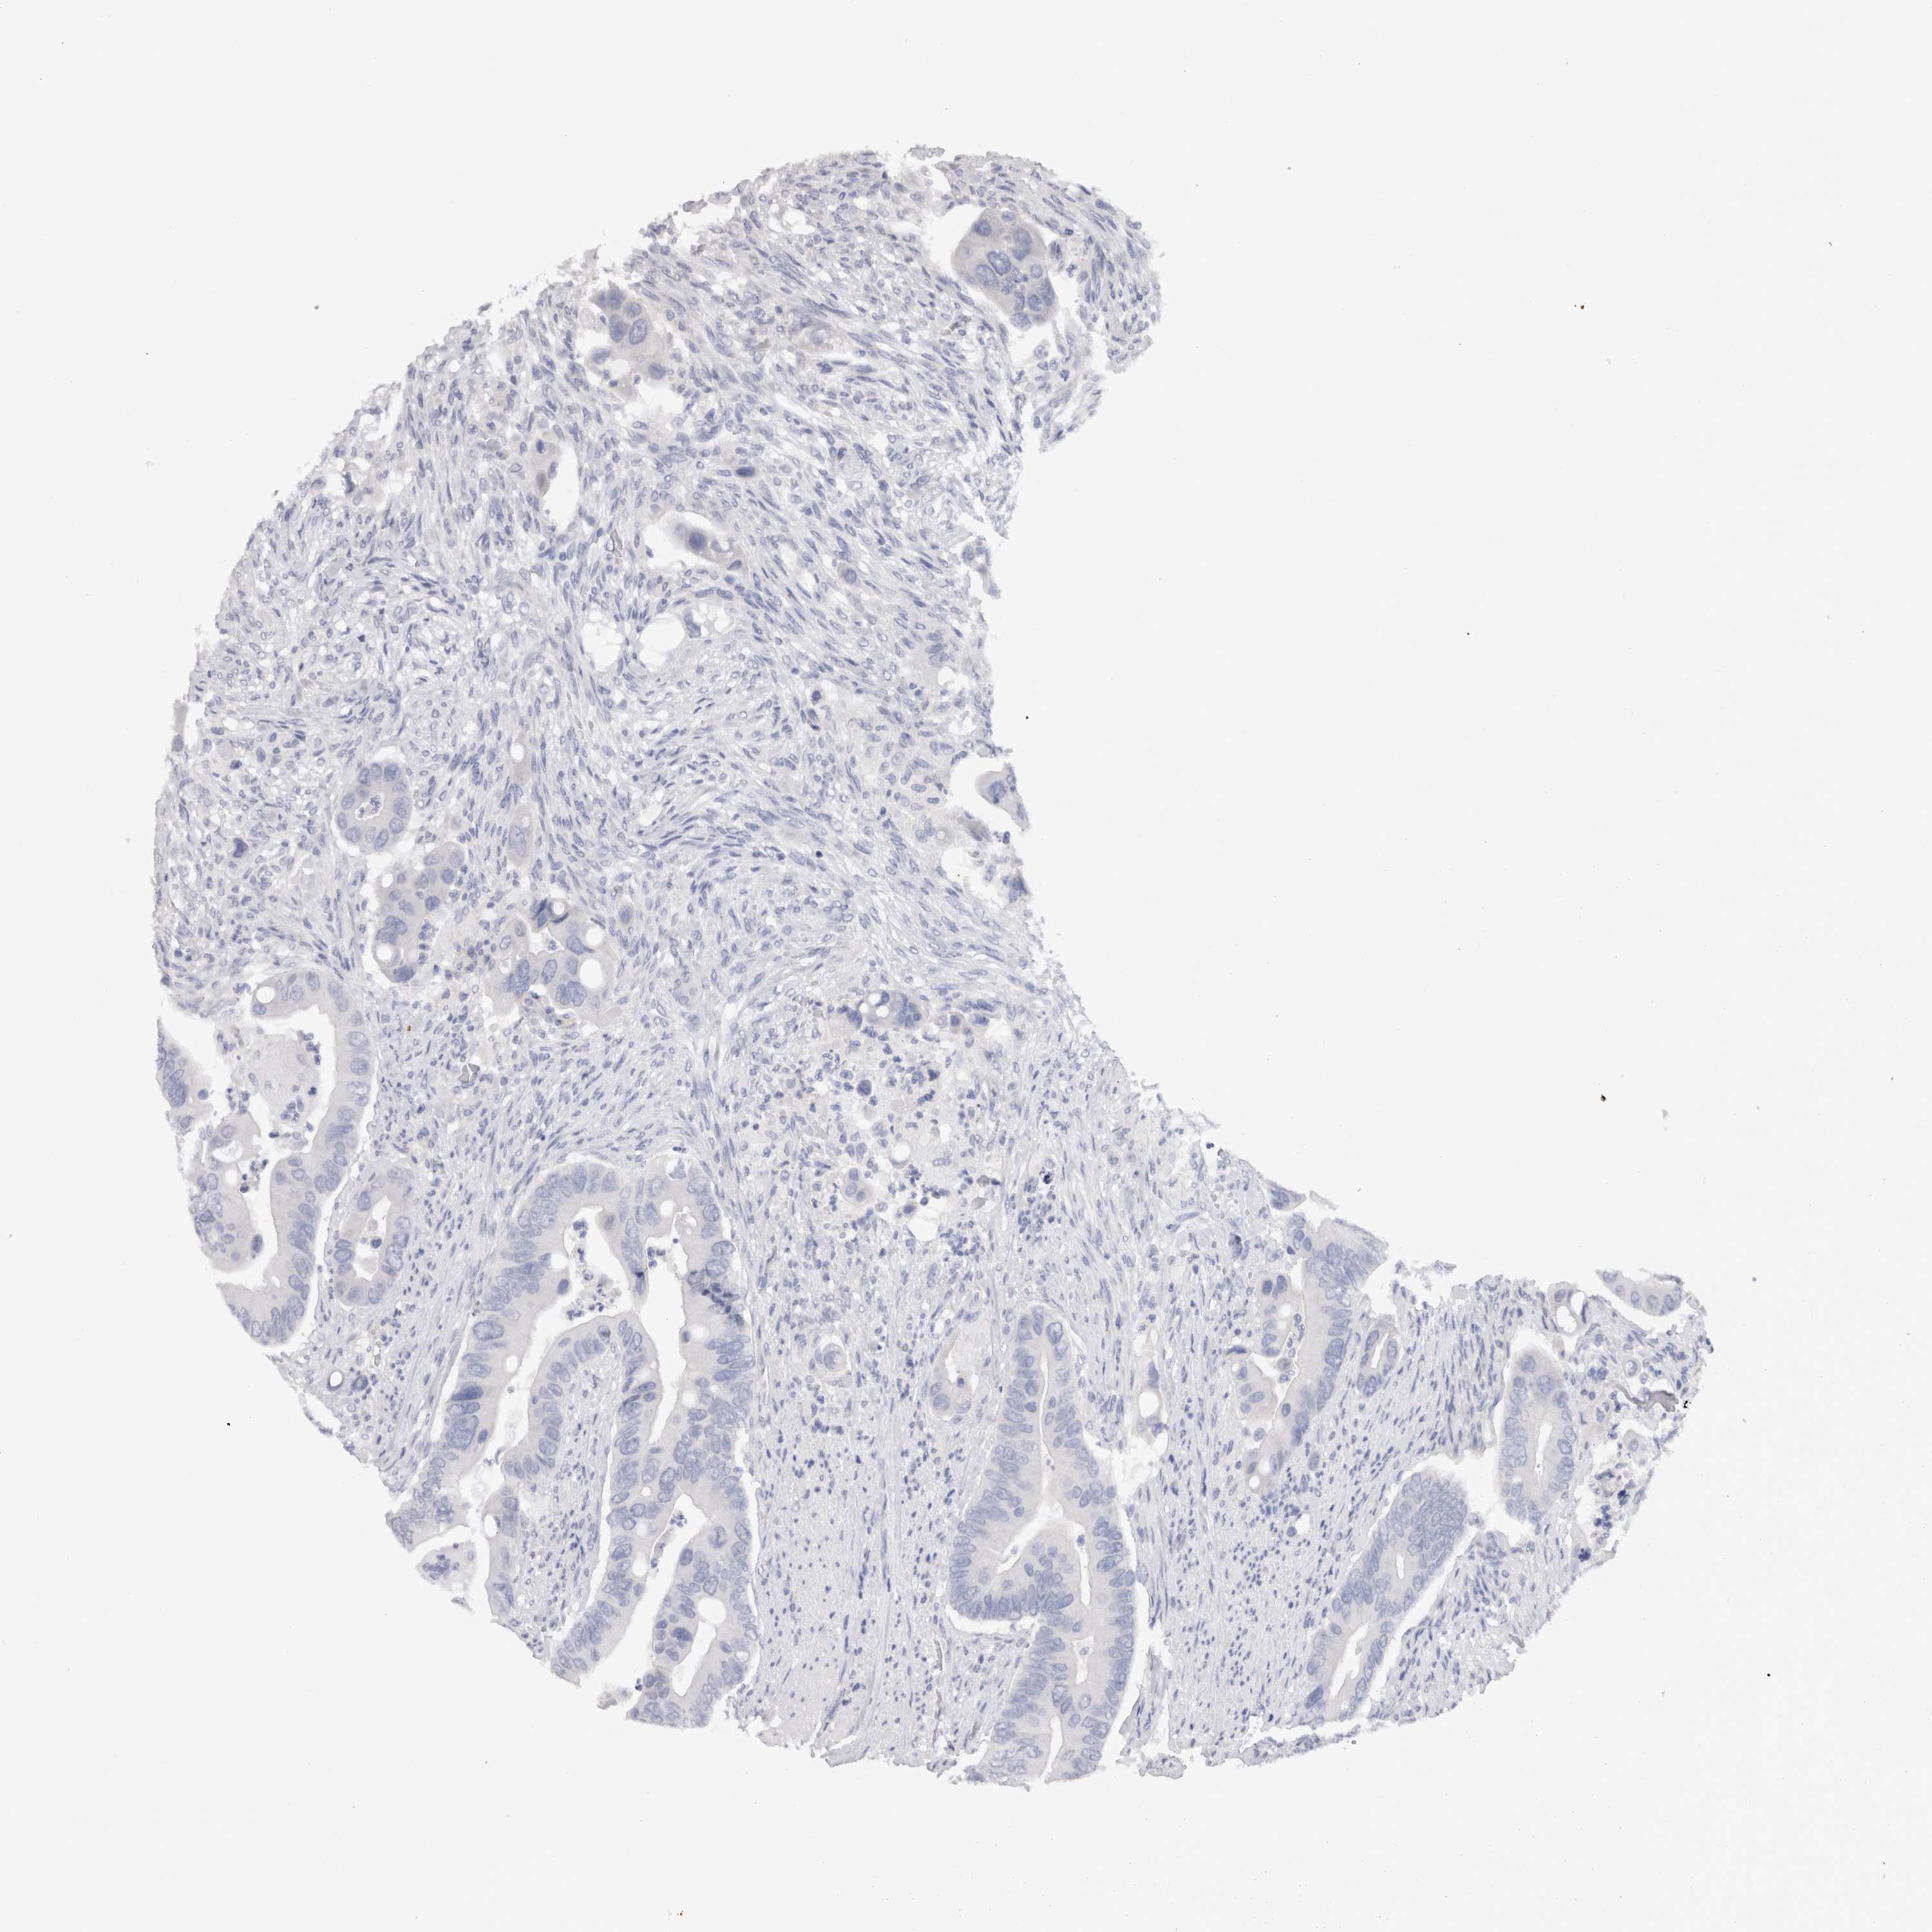

CANCER COLORECTAL CANCER Show tissue menu

Colorectal cancer

Human cancer

Colon adenocarcinoma

Rectum adenocarcinoma